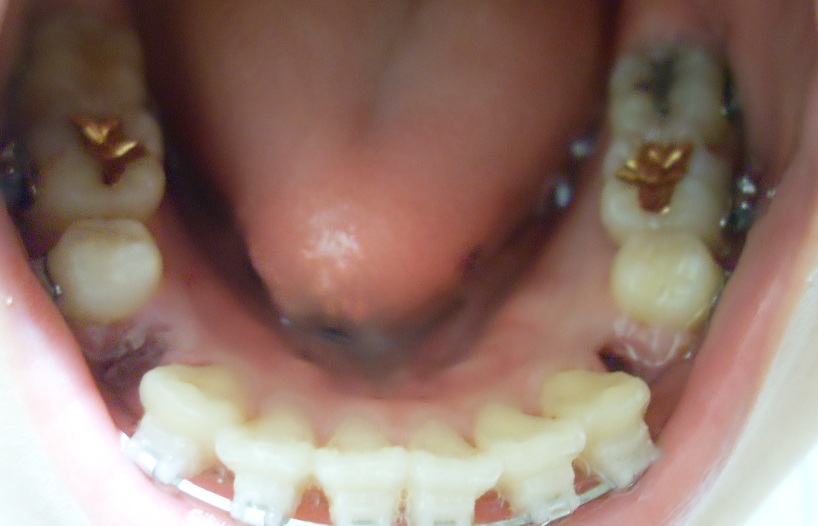

여러분 오랜만이에요~ 발치를 한주에 한번씩 하다 보니 일기를 이제야 쓰게 됬어요!!

이는 왼쪽 위아래 한개씩 먼저 빼구 일주일 뒤에 오른쪽 한개씩 뺐어요.

왼쪽 발치할 때

오라픽스 포스팅 사진 (6).JPG

(발치하고 일주일 지난 모습입니다)